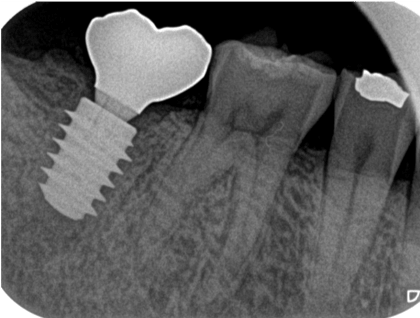

症例3【40代女性】右上74根尖病巣の治療 右上56 洞低膜を挙上しインプラント埋入

治療後(5年経過)

残存骨が5~6㎜程で、インプラント埋入には骨の高さが不足している為、ソケットリフト(骨造成)を行った。洞底膜を挙上することで、骨の高さの不足を解消。

採血のよるCGFメンブレンとAFGブロック(人工骨β‐TCPとAFGを混ぜたブロック)を填入しインプラント2本を埋入。約4ヶ月の免荷期間を経て、仮歯を装着、リハビリをし、約5ヶ月後にメタルボンド(金属焼付ポーセレン)を装着。